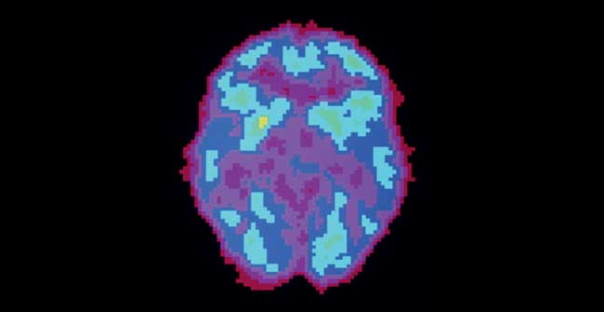

Активность мозга сильно различается не только во время бодрствования и сна — есть множество промежуточных состояний, которые можно различить во время позитронно-эмиссионной томографии.

ДЕПРИВАЦИЯ СНА. Активность мозга очень долго не спавшего человека снижена и похожа на стадию глубокого сна